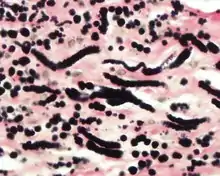

By microscopie view, there is an admixture of heavy dense bands of collagenous tissue dissected by fat and abnormal elastic fibers. The elastic fibers are often quite large and are easily identified. The elastic fibers are coarse, thick, and darkly eosinophilic, often fragmented into globules, creating a "string of pearls" or "pipe cleaner" appearance. Because of degeneration, the elastic fibers will appear as globules with a serrated or "prickled" edge.[3]

The elastic fibers will be highlighted by a Weigert or von Gieson elastic stains.[7]